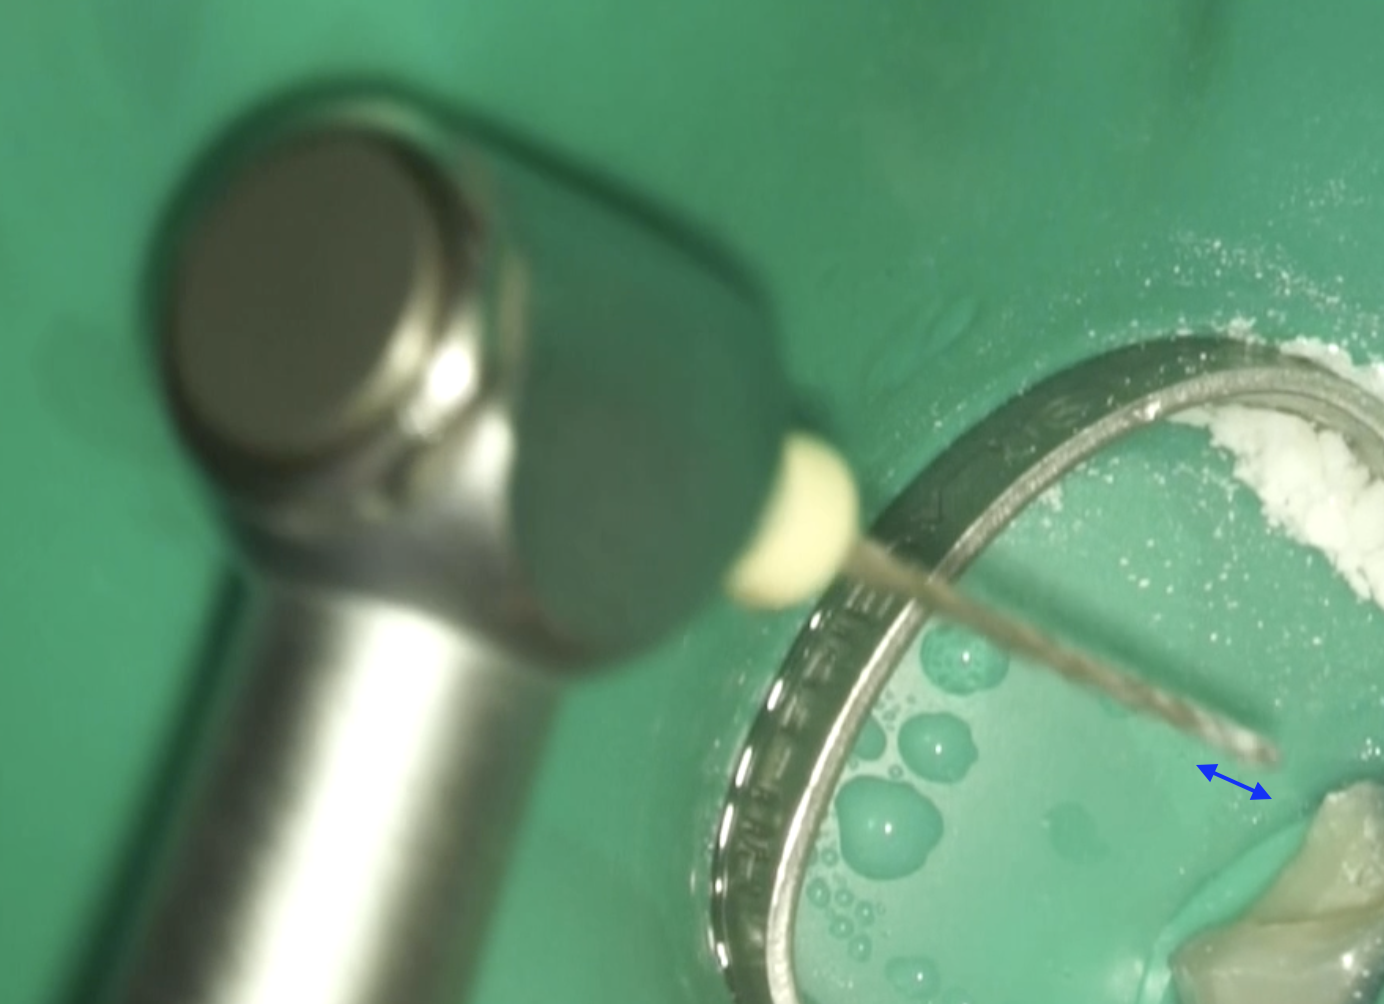

#29 RCT(2025.11.26)

穿通したFileはK File #30であった。

その後、#40.04を挿入するが

回転させる前にRubber StopがReference Pointにタッチした。

つまり、#40.04では形成不可能ということを意味する。

#60.02にサイズアップした。

この程度の形成量でこと足るだろうか?

不安を感じた私はProTaper Gold F5を使用した。

F5はわずかしか形成に寄与できていない印象だ。